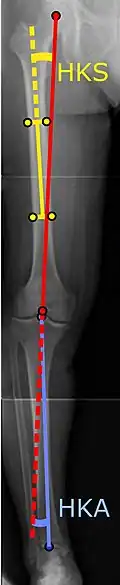

To indicate knee replacement in case of osteoarthritis, its radiographic classification and severity of symptoms both should be substantial. Such radiography should consist of weightbearing X-rays of both knees: AP, lateral, and 30 degrees of flexion. AP and lateral views may not show joint space narrowing, but the 30-degree flexion view is most sensitive for narrowing. Full-length projections also are used in order to adjust the prosthesis to provide a neutral angle for the distal lower extremity. Two angles used for this purpose are:

- Hip-knee-shaft angle (HKS),[10] an angle formed between a line through the longitudinal axis of the femoral shaft and its mechanical axis, which is a line from the center of the femoral head to the intercondylar notch of the distal femur.[12]

- Hip-knee-ankle angle (HKA),[11] which is an angle between the femoral mechanical axis and the center of the ankle joint.[12] It is normally between 1.0° and 1.5° of varus in adults.[13]

![HKA: Hip-knee-ankle angle, which is ideally between 3° varum to 3° valgum from a right angle.[62]](./_assets_/X-ray_of_HKA_angle_with_knee_prosthesis.jpg)